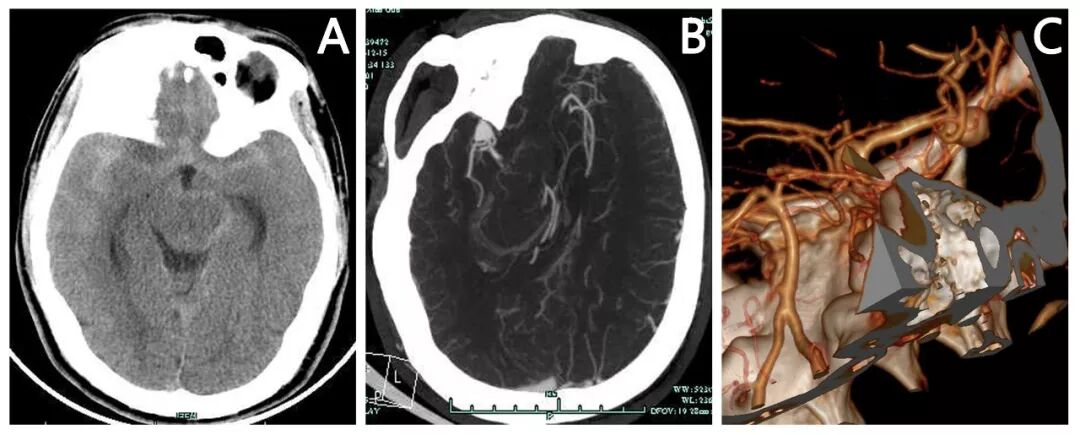

头颅CT平扫:双侧侧裂池,鞍上池,环池,纵裂池蛛网膜下腔出血。(图4A)

头颅CTA:右侧大脑中动脉动脉瘤。(图4B,C)

图4. 患者入院后行头颅CT和CTA检查结果提示右侧大脑中动脉瘤。(A)术前头颅CT平扫提示双侧侧裂池,鞍上池,环池,纵裂池蛛网膜下腔出血;(B)术前头颅CTA增强原始片提示右侧侧裂池团状异常高密度影;(C)术前头颅CTA三维重建片提示右侧大脑中动脉分叉部(主干和颞前动脉分叉部)大动脉瘤(约10mm)。

患者急性起病,头痛明显,考虑与弥漫性蛛网膜下腔出血刺激相关。目前神志意识清楚,H-H分级II级,颈抵抗阳性,考虑排除手术禁忌后需急诊行手术治疗。术前头颅CTA提示右侧大脑中动脉分叉部动脉瘤,瘤颈宽,瘤体大,分支血管被动脉瘤颈包绕,需在夹闭动脉瘤时重塑血管形态并保护各分支血管。

取右侧翼点手术入路,显微镜下沿右侧外侧裂向深部探查,于M1末端分叉部探查见动脉瘤,大小约10*8mm,瘤颈宽约7mm,朝向外下方,予周围粘连分离并充分暴露动脉瘤颈后,予临时动脉瘤夹夹闭大脑中动脉M1段(图1A),动脉瘤颈予750动脉瘤夹一枚夹闭后(图1B),荧光造影确认瘤腔内无荧光显影,但是探查见一分支血管无荧光显影(图1C),遂予调整动脉瘤夹位置和角度,夹子稍外移,此时瘤颈部分残留(图1D),再予740,720动脉瘤夹两枚完整夹闭动脉瘤残余瘤颈(图1E,F),探查见瘤颈无残留,载瘤血管及分支血管完整(图1F),再次荧光造影确认动脉瘤夹闭完全,载瘤血管及两分支血管显影良好(图1G)。

图5. 患者手术中动脉瘤夹闭及分支血管保留情况。(A)探查并分离动脉瘤周围粘连后充分暴露动脉瘤颈,予临时动脉瘤夹夹闭大脑中动脉M1段;(B)尝试予750动脉瘤夹一枚完整夹闭动脉瘤;(C)荧光造影确认瘤腔内无荧光显影,但是探查见一分支血管无荧光显影;(D)显微镜下调整动脉瘤夹位置和角度,夹子稍外移,此时瘤颈部分残留;(E)再予740动脉瘤夹一枚夹闭动脉瘤残余瘤颈,瘤颈仍少量残留;(F)最后予720迷你夹一枚完整夹闭少量残留瘤颈;(G)荧光造影确认动脉瘤夹闭完全,瘤腔内无荧光显影,载瘤血管及各分支显影良好;(H)组合夹闭技术示意图。